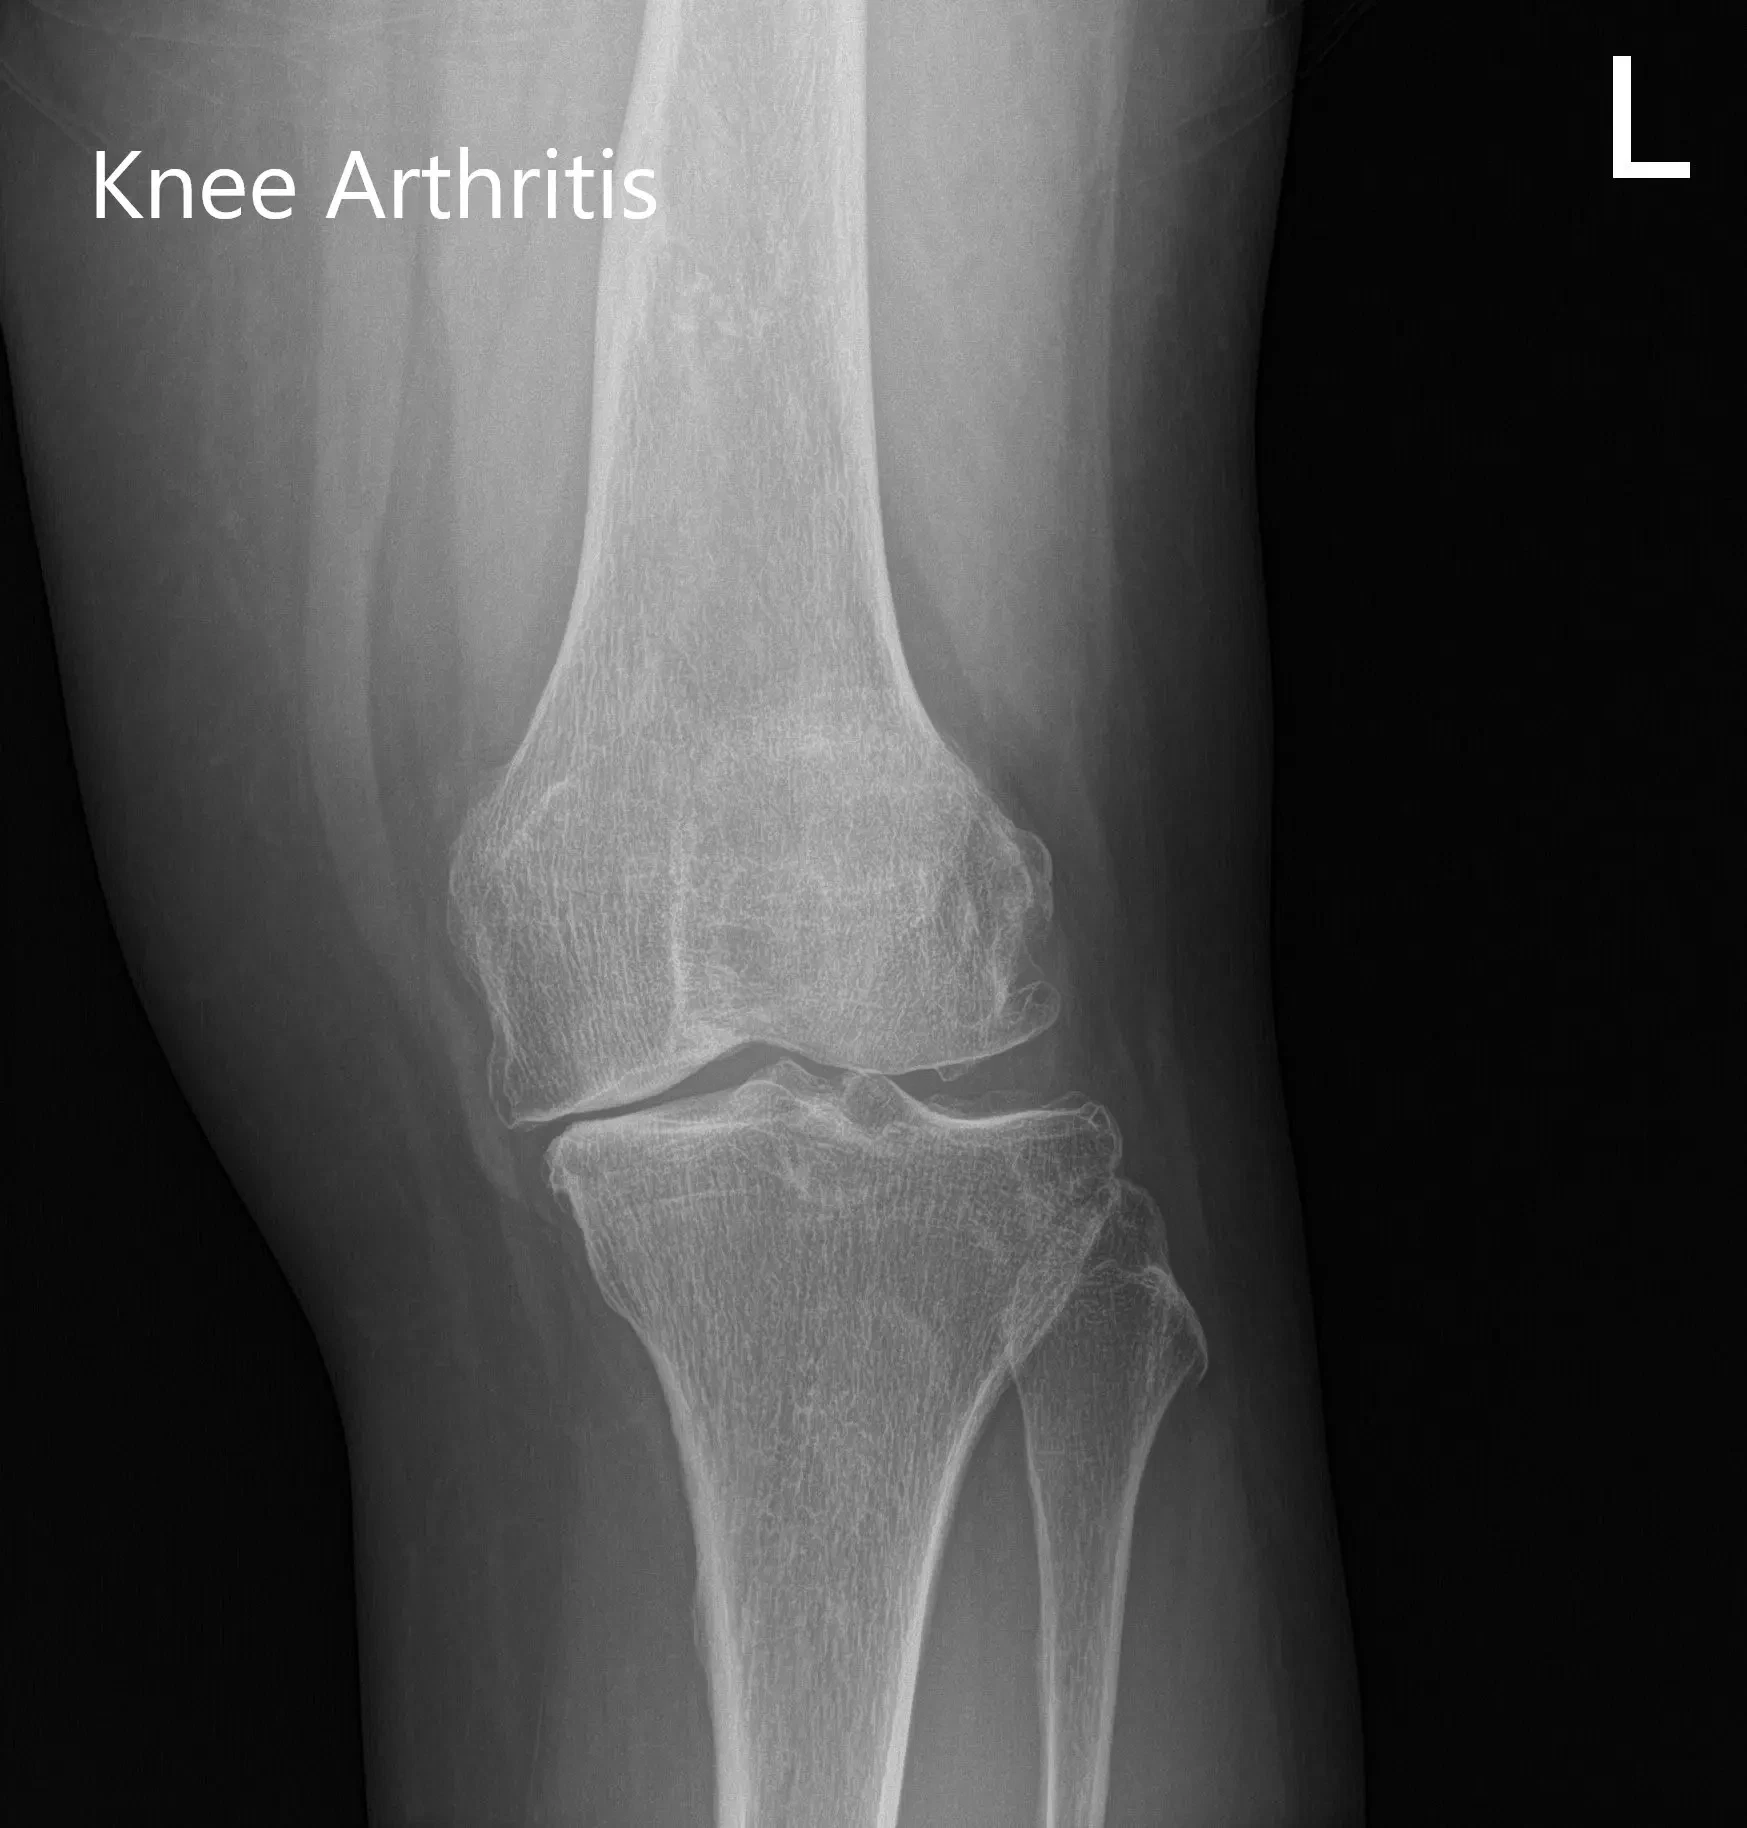

He was stressed about the pain which had recently started disturbing his sleep. He stated the pain was lifestyle limiting. Imaging studies revealed severe tricompartmental osteoarthritis. Various nonoperative and operative management options were discussed with the patient in-depth. He was deemed a candidate for custom left knee total replacement.

Preoperative X-ray showing AP and lateral images of the left knee